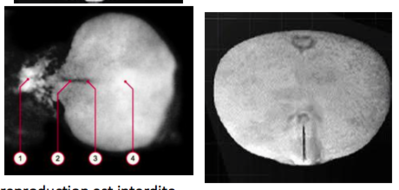

Le MEE dérive de la LP, le MEE apparait au stade 5 de carnégie, donc la LP est présente au stade 5 même si on ne le va voit pas vraiment

MAIS, ce matin l'item " la ligne primitive et le Noeud de Hensen apparaissent au stade 7 de carnégie"

Face à cet item, j'ai vraiment vraiment hésité, dans le sens où même si le stade 7 s'appelle "stade la LP" la LP apparaît avant ce stade, et à la SDR du 29 septembre, le prof avait compté une photo avec la LP dans le stade 6